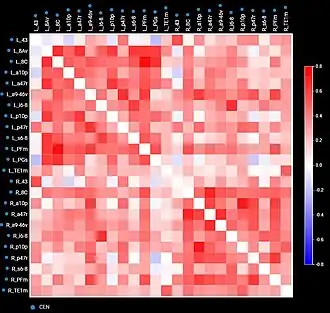

By comparing diseased and healthy connectomes, we can gain insight into certain psychopathologies, such as neuropathic pain, and potential therapies for them. Generally, the field of neuroscience would benefit from standardization and raw data. For example, connectome maps can be used to inform computational models of whole-brain dynamics.[75] Current neural networks mostly rely on probabilistic representations of connectivity patterns.[76] Connectivity matrices (checkerboard diagrams of connectomics) have been used in stroke recovery to evaluate the response to treatment via Transcranial Magnetic Stimulation.[77] Similarly, connectograms (circular diagrams of connectomics) have been used in traumatic brain injury cases to document the extent of damage to neural networks.[78][79]

As a network or graph

A connectome can be viewed as a graph, and the rich tools, definitions and algorithms of graph theory and network science can be applied to these graphs. In case of a micro-scale connectome, the nodes of this network (or graph) are the neurons, and the edges correspond to the synapses between those neurons. For the macro-scale connectome, the nodes correspond to the ROIs (regions of interest), while the edges of the graph are derived from the axons interconnecting those areas. Thus connectomes are sometimes referred to as brain graphs, as they are indeed graphs in a mathematical sense which describe the connections in the brain (or, in a broader sense, the whole nervous system).

One group of researchers (Iturria-Medina et al., 2008)[98] has constructed connectome data sets using diffusion tensor imaging (DTI)[99][100] followed by the derivation of average connection probabilities between 70 and 90 cortical and basal brain gray matter areas. All networks were found to have small-world attributes and "broad-scale" degree distributions. An analysis of betweenness centrality in these networks demonstrated high centrality for the precuneus, the insula, the superior parietal and the superior frontal cortex. Another group (Gong et al. 2008)[101] has applied DTI to map a network of anatomical connections between 78 cortical regions. This study also identified several hub regions in the human brain, including the precuneus and the superior frontal gyrus.

Hagmann et al. (2007)[102] constructed a connection matrix from fiber densities measured between homogeneously distributed and equal-sized ROIs numbering between 500 and 4000. A quantitative analysis of connection matrices obtained for approximately 1,000 ROIs and approximately 50,000 fiber pathways from two subjects demonstrated an exponential (one-scale) degree distribution as well as robust small-world attributes for the network. The data sets were derived from diffusion spectrum imaging (DSI) (Wedeen, 2005),[103] a variant of diffusion-weighted imaging[104][105] that is sensitive to intra-voxel heterogeneities in diffusion directions caused by crossing fiber tracts and thus allows more accurate mapping of axonal trajectories than other diffusion imaging approaches (Wedeen, 2008).[106] The combination of whole-head DSI datasets acquired and processed according to the approach developed by Hagmann et al. (2007)[102] with the graph analysis tools conceived initially for animal tracing studies (Sporns, 2006; Sporns, 2007)[107][108] allow a detailed study of the network structure of human cortical connectivity (Hagmann et al., 2008).[109] The human brain network was characterized using a broad array of network analysis methods including core decomposition, modularity analysis, hub classification and centrality. Hagmann et al. presented evidence for the existence of a structural core of highly and mutually interconnected brain regions, located primarily in posterior medial and parietal cortex. The core comprises portions of the posterior cingulate cortex, the precuneus, the cuneus, the paracentral lobule, the isthmus of the cingulate, the banks of the superior temporal sulcus, and the inferior and superior parietal cortex, all located in both cerebral hemispheres.